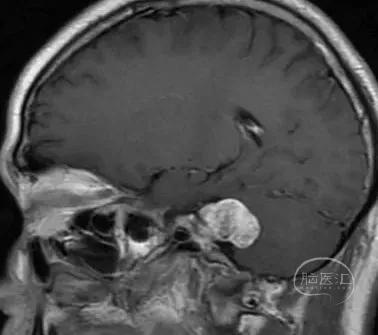

患者:女, 42y

右侧面部麻木半年余

右侧听力下降伴耳鸣4月余

核磁共振检查发现右侧桥小脑角区占位

肿瘤最大直径约2.6 cm

术前影像

术前影像资料

(肿瘤长入内听道内较深-9.1mm)